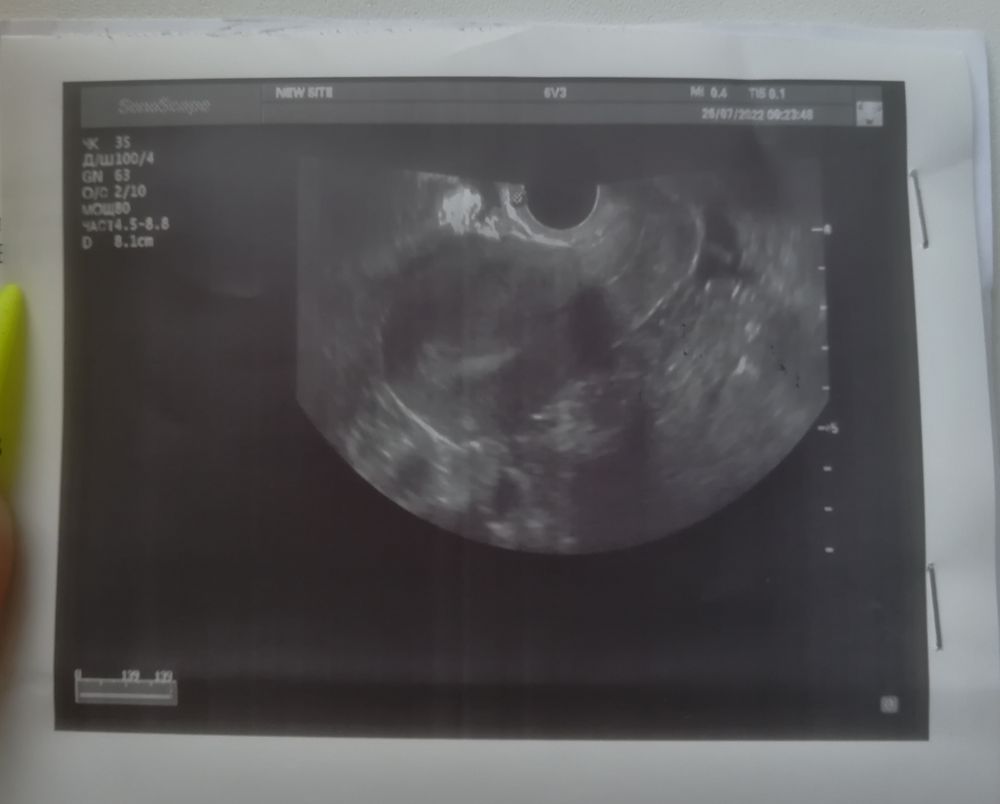

Добрый день девочки. Вообщем ситуация такая, сегодня 20 дц, цикл 28 дней, обычно болит грудь после овуляции всегда, но не в этом месяце, я решила сходить на узи т.к думала что цикл ановуляторный, но узи это не подтвердило и в итоге сказали, что либо

была овуляция двойная и два жёлтых тела, либо одно жт и один дф и овуляция ещё будет. Цикл стабильный, задержек не бывает, максимум 1 день. И как при 28 дневном цикле возможна овуляция на 20 дц, а то и позже, если предположить что это всё таки дф и он 16 мм. Может кто разбирается, что на фото всё таки? Заранее всем спасибо. 🙏